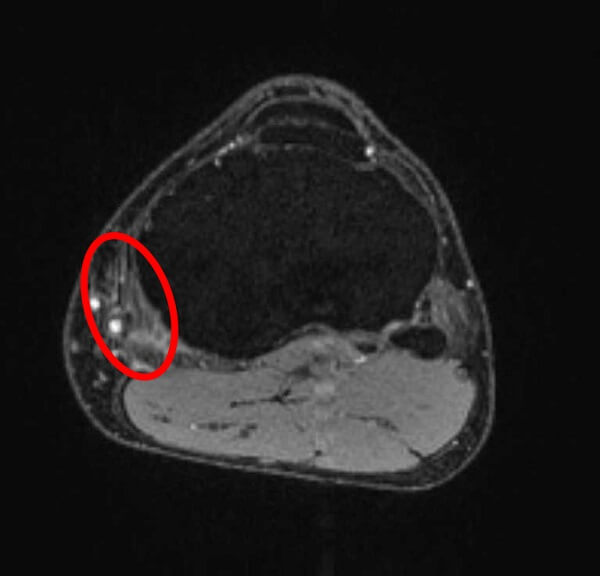

MRI画像

鵞足の腱周囲の炎症による輝度上昇(白く見える)が確認できる。